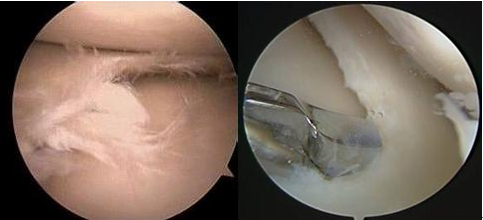

近些年,关节镜技术的发展及治疗日新月异,非常适用于半月板损伤的治疗,半月板边缘撕裂可行缝合修复,通常进行半月板部分切除,保留未损伤的部分。对早期怀疑半月板损伤者可行急诊关节镜检查,早期处理半月板损伤,缩短疗程,提高治疗效果,减少损伤性

关节炎

的发生。通过关节镜手术创伤小,恢复快,为现在半月板损伤的首选治疗方法。